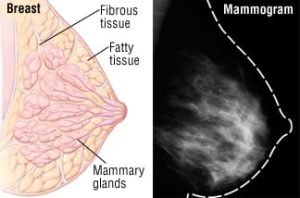

A mammogram is an image of the breast obtained by X-ray. Mammograms are used by doctors to detect early indications of breast cancer. Frequent mammograms can detect breast cancer at an early stage, often even three years before any symptoms appear.

In front of a unique X-ray machine, you will stand. Your breast will be placed on a plastic plate by a technologist. Your breast will be firmly pressed from above by another plate. The breast will be held still during the X-ray by the plates’ ability to flatten it. There will be some strain on you. To create a side view of the breast, repeat these procedures. In the same manner, the other breast will be X-rayed. After that, you’ll have to wait while the technologist reviews the X-rays to make sure no more photographs need to be taken. Remember that the technologist is unable to provide you with the results of your mammography. Because every woman’s breasts are unique, every woman’s mammography may appear slightly different.